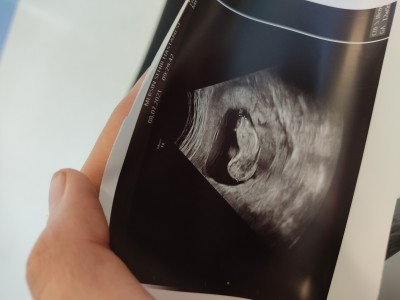

Cinseyet tahmininde bulunabilir misiniz yoksa daha erken mi ?

Gebelik haftası 11+2

Nub teorisine göre kıza benziyor

Nuba göre kız sanki

Erken ama erkeğin yüzü daha belirgin oluyordu sanırım bu kız olabilir

Kiz canım vallahi doktorlarda nub teorisine göre söylüyor bana 100 100 kız dedi 12 haftada çıkıntı gibi birşey var duzse kız yukarı taraf bakıyorsa erkek Bu bebekte kız sende öğrenince yaz bak kız diyecek doktor nen 23 hafta oldu kiz hale  degismedi